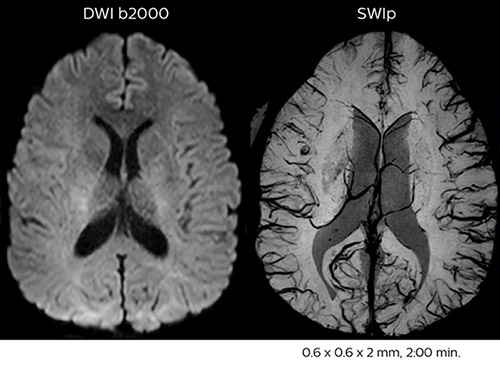

In this patient with acute right motor deficit and aphasia, the b2000 diffusion weighted image is normal. The SWIp image demonstrates more prominent veins in the right hemisphere, which could reflect increased deoxyhemoglobin contents. Fast ASL shows low CBF regions in the left frontal lobe. A follow-up ASL after one hour demonstrates high CBF values in the same area. The final diagnosis was migraine with aura.

Dr. Savatovsky appreciates the improvements and flexibility that Elition with Compressed SENSE and MultiBand SENSE provides, particularly for stroke patients. “For stroke, it allows us to cut about 5 minutes off of our stroke protocol, or to keep the same acquisition time and get more insights.” The ability to perform more sequences can help in making a swift and confident diagnosis. “For example, our stroke cases usually include the regular sequences that every center does (b1000 diffusion, FLAIR, time-of-flight angiography), but we also image supra aortic vessels, and we can replace a gradient echo sequence with a fast 50-second susceptibility-weighted sequence, and all of this doesn’t add much time. because all the regular sequences are accelerated on Elition.” “The time savings with Compressed SENSE and MultiBand SENSE make it easier to add sequences to give us additional insights. Depending on the context and the first results, we might add a DSC perfusion to assess the ischemic penumbra, an ASL perfusion to help find an alternative cause in case of normal diffusion, or add a high-resolution T1 sequence for a stroke patient, to quickly assess wall imaging in emergency cases. The additional sequences can help improve patient management, because we can already consider some alternative diagnoses if the morphological MRI is normal.”

Using MultiBand SENSE allowed the staff to improve their diffusion quality. “Our diffusion sequence was already fast before, about 40 seconds. Now with Elition, it still lasts 40 seconds, but we improved the spatial resolution by 0.2 mm and use high b-values to be more sensitive to visualize changes related to acute stroke,” says Dr. Savatovsky. “We now also developed a high resolution DTI sequence (1.3 x 1.3 x 2 mm) that can be reformatted and takes 2 to 5 minutes depending on the coverage. We use it every time we have a doubt, or when we expect the diffusion to be abnormal but don’t see that on the fast sequence. We occasionally spot small ischemic infarctions that would not have been visible with the regular diffusion sequence.”